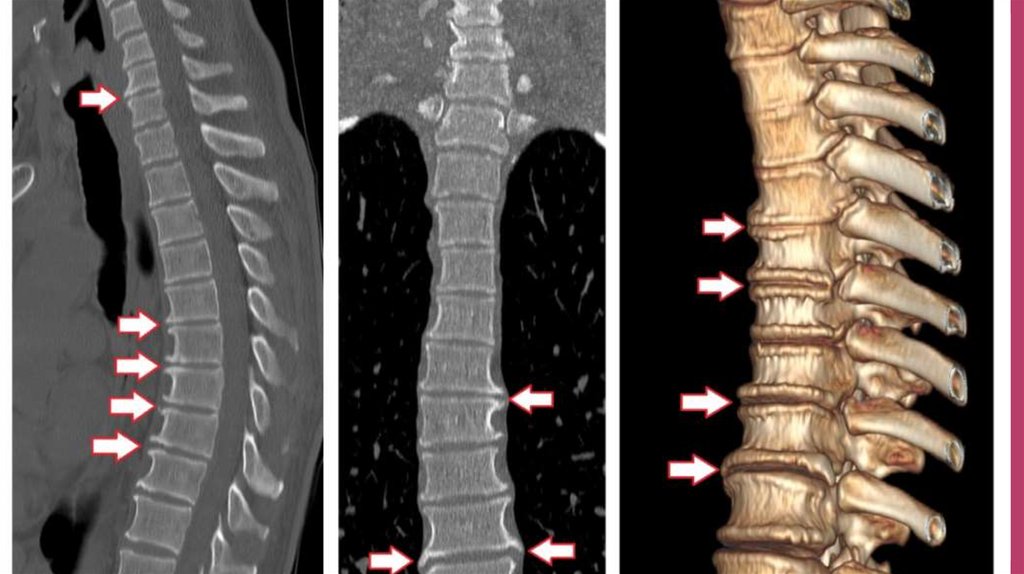

Для точно определения первопричин и места локализации

дегенеративных процессов проводят рентгенографию, компьютерную

томографию, МРТ. При исследовании очагов воспаления рядом с

дугоотросчатыми суставами используют радиоизотопное сканирование

спины.

А для обнаружения синдрома позвоночной артерии применяют МСКТангиографию. В редких ситуациях вводят диагностические блокады.

Если у пациента произошло уменьшение или полное исчезновение

болевого синдрома, то у него точно есть спондилоартроз.